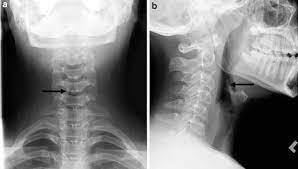

Foreign Bodies On Lateral Neck Radiographs In Adults Imaging Findings And Common Pitfalls Radiographics from pubs.rsna.org For instance, voice changes may be a sign of laryngeal (voice box) cancer, but they would rarely indicate cancer of the pharynx. Please help, i am terrified! If the fna doesn't show cancer, it only means that cancer was not found in that lymph node. The most common symptom of thyroid cancer is a hard lump on the neck—but most patients experience no symptoms at all. How does a colon cancer look like? Two in three cases of thyroid cancer occur in people under age 55, and 75%. Ultrasound is useful in a few instances. This mass will look like a white spot on your lungs, while the lung itself will appear black.

It is often the first imaging test a doctor will order if lung or heart disease is suspected. Each subtype of throat cancer has its own criteria for each stage. The bone at the site of the cancer may look ragged instead of solid. The appearance of throat cancer on the other hand depends on the part of the throat that is affected by cancer and the stage of its development. To evaluate respiratory conditions like asthma, bronchitis, and pneumonia, heart conditions, broken ribs, and to look for fluid and tumors within the chest cavity.

The appearance of throat cancer on the other hand depends on the part of the throat that is affected by cancer and the stage of its development. Lung cancer tumors look like white round circles on cxr. Later stages indicate more advanced cancer, with stage iv being the most advanced. For instance, voice changes may be a sign of laryngeal (voice box) cancer, but they would rarely indicate cancer of the pharynx. Your voice box sits just below your throat and also is susceptible to throat cancer. Let's talk about throat cancer. This mass will look like a white spot on your lungs, while the lung itself will appear black. Sometimes doctors can see a tumor around the defect in the bone that might extend into nearby tissues (such as muscle. If they notice signs of a problem, they'll look carefully inside your mouth and throat, sometimes with a special lighted tool, and may feel your jaw and neck for lumps or patches. Lung cancer and throat cancer sometimes occur at the same time. The most sensitive way to detect throat cancer is to have an. The leukoplakia is apparent under imaging test and cannot be rubbed off. The most common symptom of thyroid cancer is a hard lump on the neck—but most patients experience no symptoms at all.